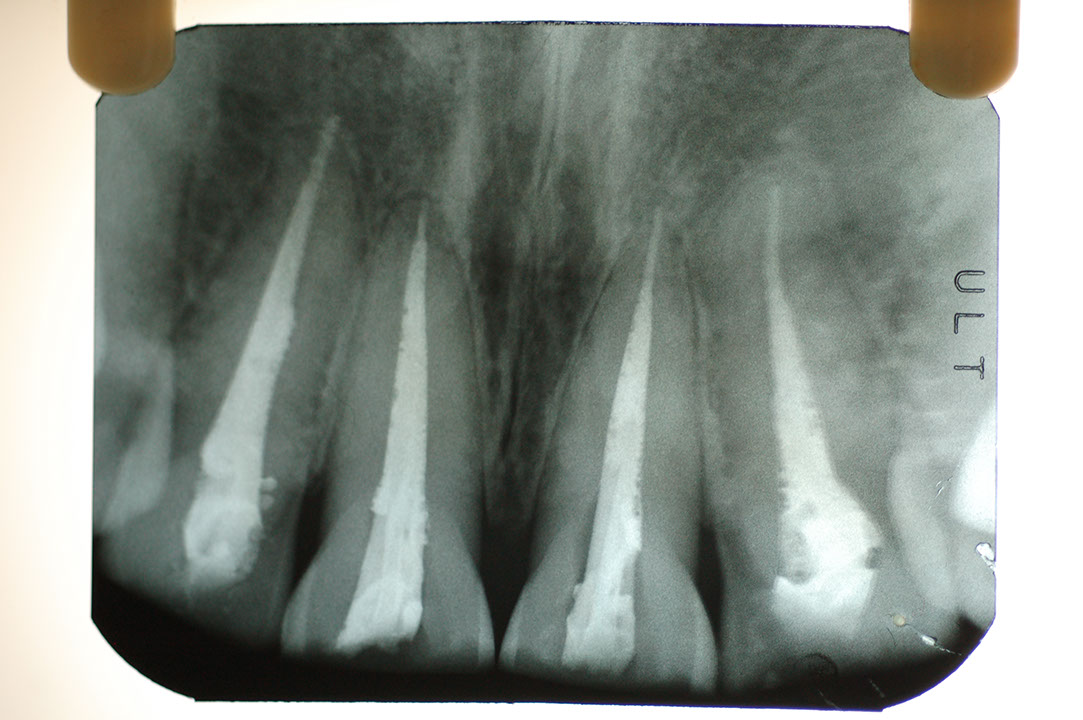

光牙醫